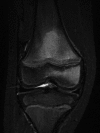

Limp is a common clinical presentation in children, seen both in acute and community practice. The incidence is thought to vary between countries with suggested figures between 1.5 and 3.6 cases of non-traumatic limp per 1000 children. The authors present a case of a 6-year-old girl who attended our accident and emergency department with limp. It has been suggested that the most common diagnoses in our patient's age group are transient synovitis, septic arthritis, osteomyelitis, Perthe's disease and fractures or soft tissue injuries. Surprisingly our patient was diagnosed with haemophagocytic lymphohistiocytosis, for which limp is not a recognised presenting feature.